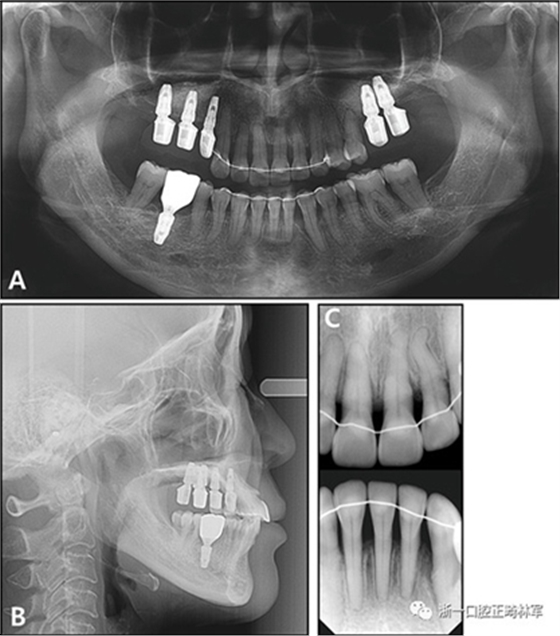

全景X線片顯示了牙槽骨支持的整體下降和下頜左側(cè)側(cè)切牙區(qū)廣泛的骨質(zhì)喪失。頭影測量分析表明是具有正常垂直面形,上頜切牙唇向錯位以及與Rickett‘s E線相關(guān)的上唇前凸的骨性I類關(guān)系(圖3和4;表II)?;颊弑辉\斷為骨骼I類錯合畸形,伴有慢性中度牙周炎和多顆牙齒缺失。

圖3. 治療前X線片:A,牙周治療前的全景X光片; B,牙周治療后的全景X光片; C,側(cè)位X線片; D,根尖片。

治療后全景X線片顯示與初始值相比,沒有顯著的骨喪失。上頜尖牙被推入并向遠(yuǎn)中移動,導(dǎo)致在根尖周觀察到尖牙骨水平的改善。在拔除的下頜側(cè)切牙周圍出現(xiàn)嚴(yán)重的牙槽骨缺損,并且尖牙近中側(cè)的牙周病引起了骨內(nèi)缺損。在關(guān)閉間隙期間,下頜中切牙和尖牙被移向了骨質(zhì)缺損區(qū)域,并且側(cè)切牙周圍的缺損已被恢復(fù)(圖12)。此外,尖牙的牙齦退縮臨床上也得到了改善(圖13)。

圖12.治療后的X線片:A,全景X光片;B,頭影側(cè)位片;C,根尖片

根據(jù)治療前后的根尖X光片,可以發(fā)現(xiàn)存在3.5mm顯著改善的放射線骨水平(圖15),并且臨床上牙周袋深度減少(表IV)。此外,力的推入性成分在向遠(yuǎn)中移動期間誘導(dǎo)了上頜切牙的推入,并且在根尖X線照片上看到牙槽骨水平的改善。